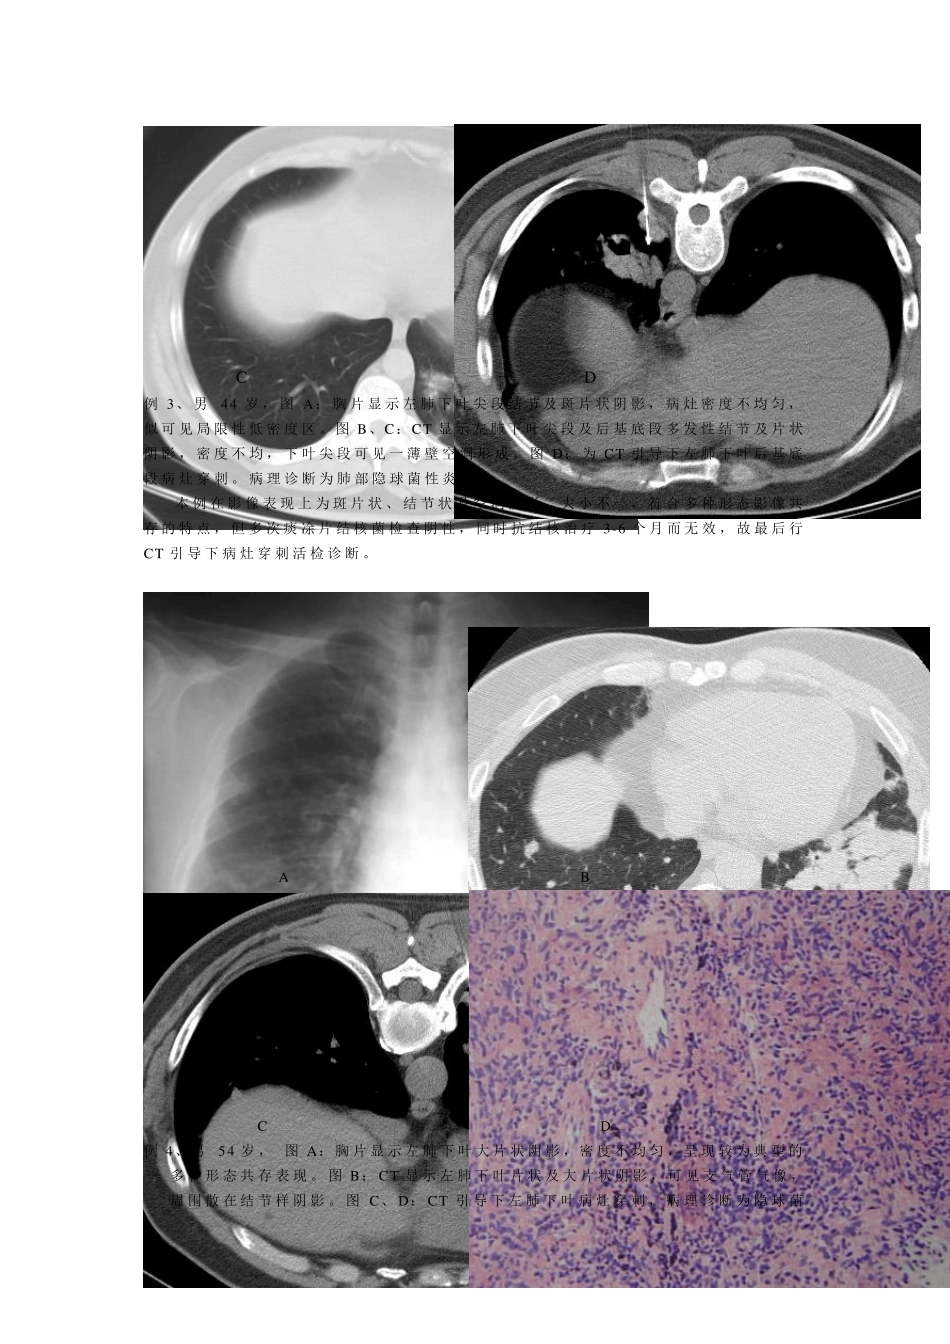

1 一、 与肺结核表现极其相似的肺部炎性病变 尽 管 肺 结 核 的 表 现 多 具 有 一 定 特 点 , 但 部 分 肺 部 炎 症 性 病 变 在 影 像 上 却往 往 与 肺 结 核 的 表 现 极 其 相 似 , 虽 然 两 者 病 理 解 剖 学 构 成 迥 然 不 同 , 但 呈 现相 同 影 像 表 现 者 在 临 床 屡 见 不 鲜 。 因 此 , 肺 部 炎 症 性 病 变 应 该 是 临 床 诊 断 中最 常 见 和 最 需 要 与 肺 结 核 病 变 鉴 别 的 疾 病 , 尤 其 是 继 发 性 肺 结 核 。 在 影 像 诊 断 中 , 鉴 于 肺 结 核 和 肺 部 炎 症 性 病 变 病 理 变 化 的 不 同 , 通 常 是立 足 于 评 价 肺 部 影 像 以 多 种 形 态 共 存 的 特 点 来 确 定 继 发 性 肺 结 核 的 诊 断 , 而以 相 对 均 一 性 的 特 点 来 诊 断 非 特 异 性 炎 性 病 变 。 由 于 引 起 肺 部 炎 症 性 病 变 的病 原 很 多 ,包 括 细 菌 、病 毒 和 霉 菌 等 ,仅 从 影 像 学 角 度 有 时 也 往 往 难 以 确 诊 ,应 该 密 切 结 合 临 床 表 现 及 各 种 相 关 实 验 室 检 查 结 果 进 行 诊 断 , 必要 时 可进 行抗感染试验 性 治疗, 以 进 行 动态 观察。 现 将在 影 像 表 现 上 与 肺 结 核 病 变 极 其 相 似 的 肺 部 炎 症 性 病 变 等 例举如下: A B C 例1、男 30 岁 图A 胸片显示两 肺 弥漫性 粟粒结 节影 ,以 两 中 下肺 野分 布为甚,部 分结 节有 融合 表 现 。 图B、 C:CT 扫描显示两 中 下肺 弥漫分 布的 粟粒结 节影 , 呈 对 称性 较均 匀分 布, 结 节边缘大多 数清楚, 仅 基底段结 节有 融合 倾向, 并可见 小叶间隔增厚。 本例在 影 像 诊 断 上 首先考虑为血行 播散性 肺 结 核 , 但 各 种 肺 结 核 相 关 检 查 均 阴性 ,最 后经血清肺 军团菌 抗体检 测多 组指标阳性 , 最 终诊 断 为“ 军团菌 肺 炎 ” 。 2 A B C D 例2、 女 27 岁 图A 胸片显示左肺上叶尖后段大片状阴影,病灶密度不均匀,似有结节样改变,与继发...